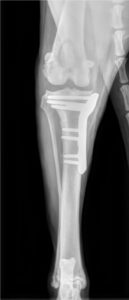

Les affections orthopédiques du chien et du chat sont nombreuses : rupture du ligament croisé, luxation de rotule, anomalies articulaires de type dysplasie, ostéochondrose, entorse ou luxation…

Elles peuvent nécessiter une prise en charge chirurgicale ou une gestion médicale, les indications sont évaluées lors d’une consultation.

Les traumatismes des membres sont fréquents : chat qui chute d’un balcon, chien heurté par une voiture, accident de chasse, etc… Beaucoup de fractures nécessitent un traitement chirurgical (ostéosynthèse par broche ou plaque par exemple), rare sont les fractures sur lesquelles un plâtre ou une résine peuvent être posées.